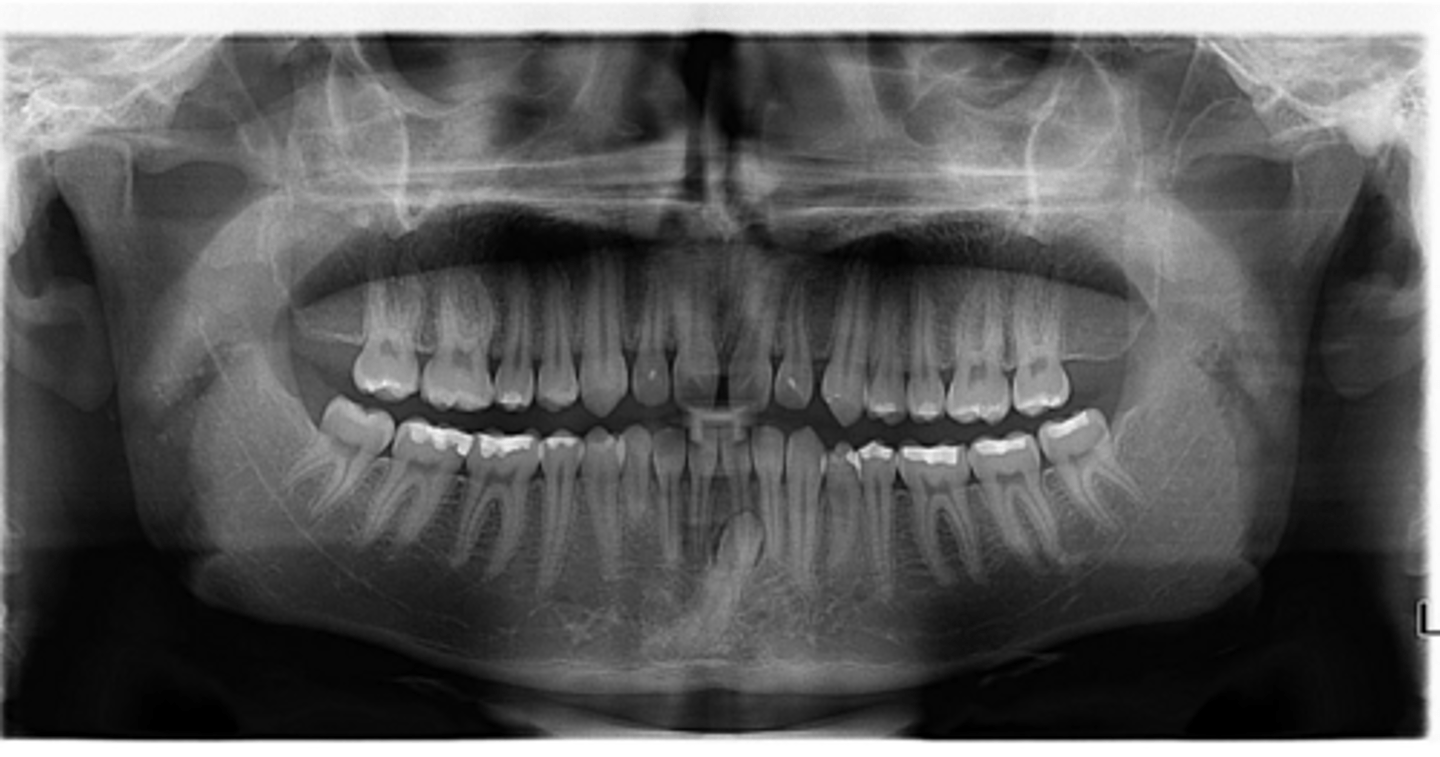

No

Are there any supernumerary teeth?

Yes - upper right near the premolar

Are there any retained primary teeth?

Any impacted teeth?

Can't see, so can't say

Symmetric condyles?

Yes - #2, also #27?

Dilacerated roots?

Are there congenitally missing teeth in the maxillary arch?

Are there congentially missing teeth in the mandibular arch?

Any supernumerary teeth?

Yes - mandibular second molars

Yes

Are the condyles symmetrical?

Maybe in the upper molars

Are there any dilacerated roots?